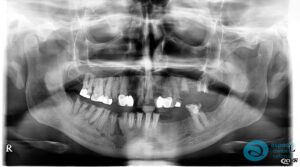

Before Implant-Retained Overdentures Xray – Dental Implants Milton Keynes – Aspects Dental Case Study 19